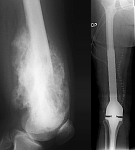

• Tumor total endoprosthesis (TEP) of all large joints and bones

• Reconstruction of bone defects by biological procedures (from spongiosaplasty to bone transfer)